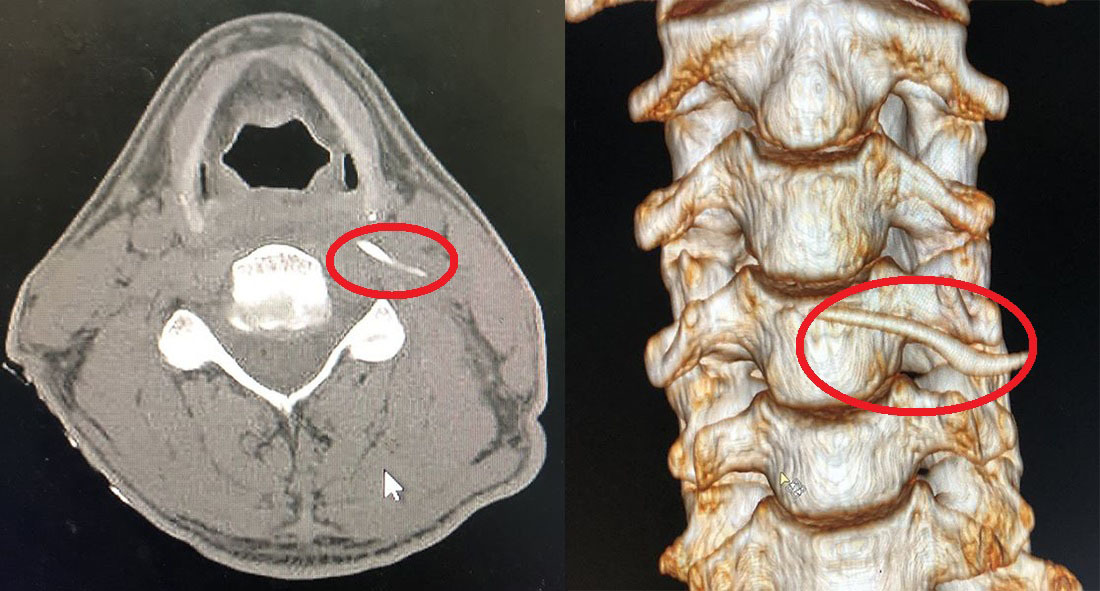

Hình ảnh cắt lớp vi tính và Xquang xương cá trong cổ anh Nam. Ảnh: Vietnamnet |

Tại khoa Tai Mũi Họng, BV Hữu nghị Đa khoa Nghệ An, qua hình ảnh chụp cắt lớp vi tính và X-quang, các bác sĩ phát hiện chiếc xương sắc nhọn dài gần 4 cm đâm sâu vào vị trí thành sau hầu thanh quản, nằm trong khoang cạnh hầu và ngang mức bờ trên sụn giáp, sát cột sống cổ và miệng thực quản.